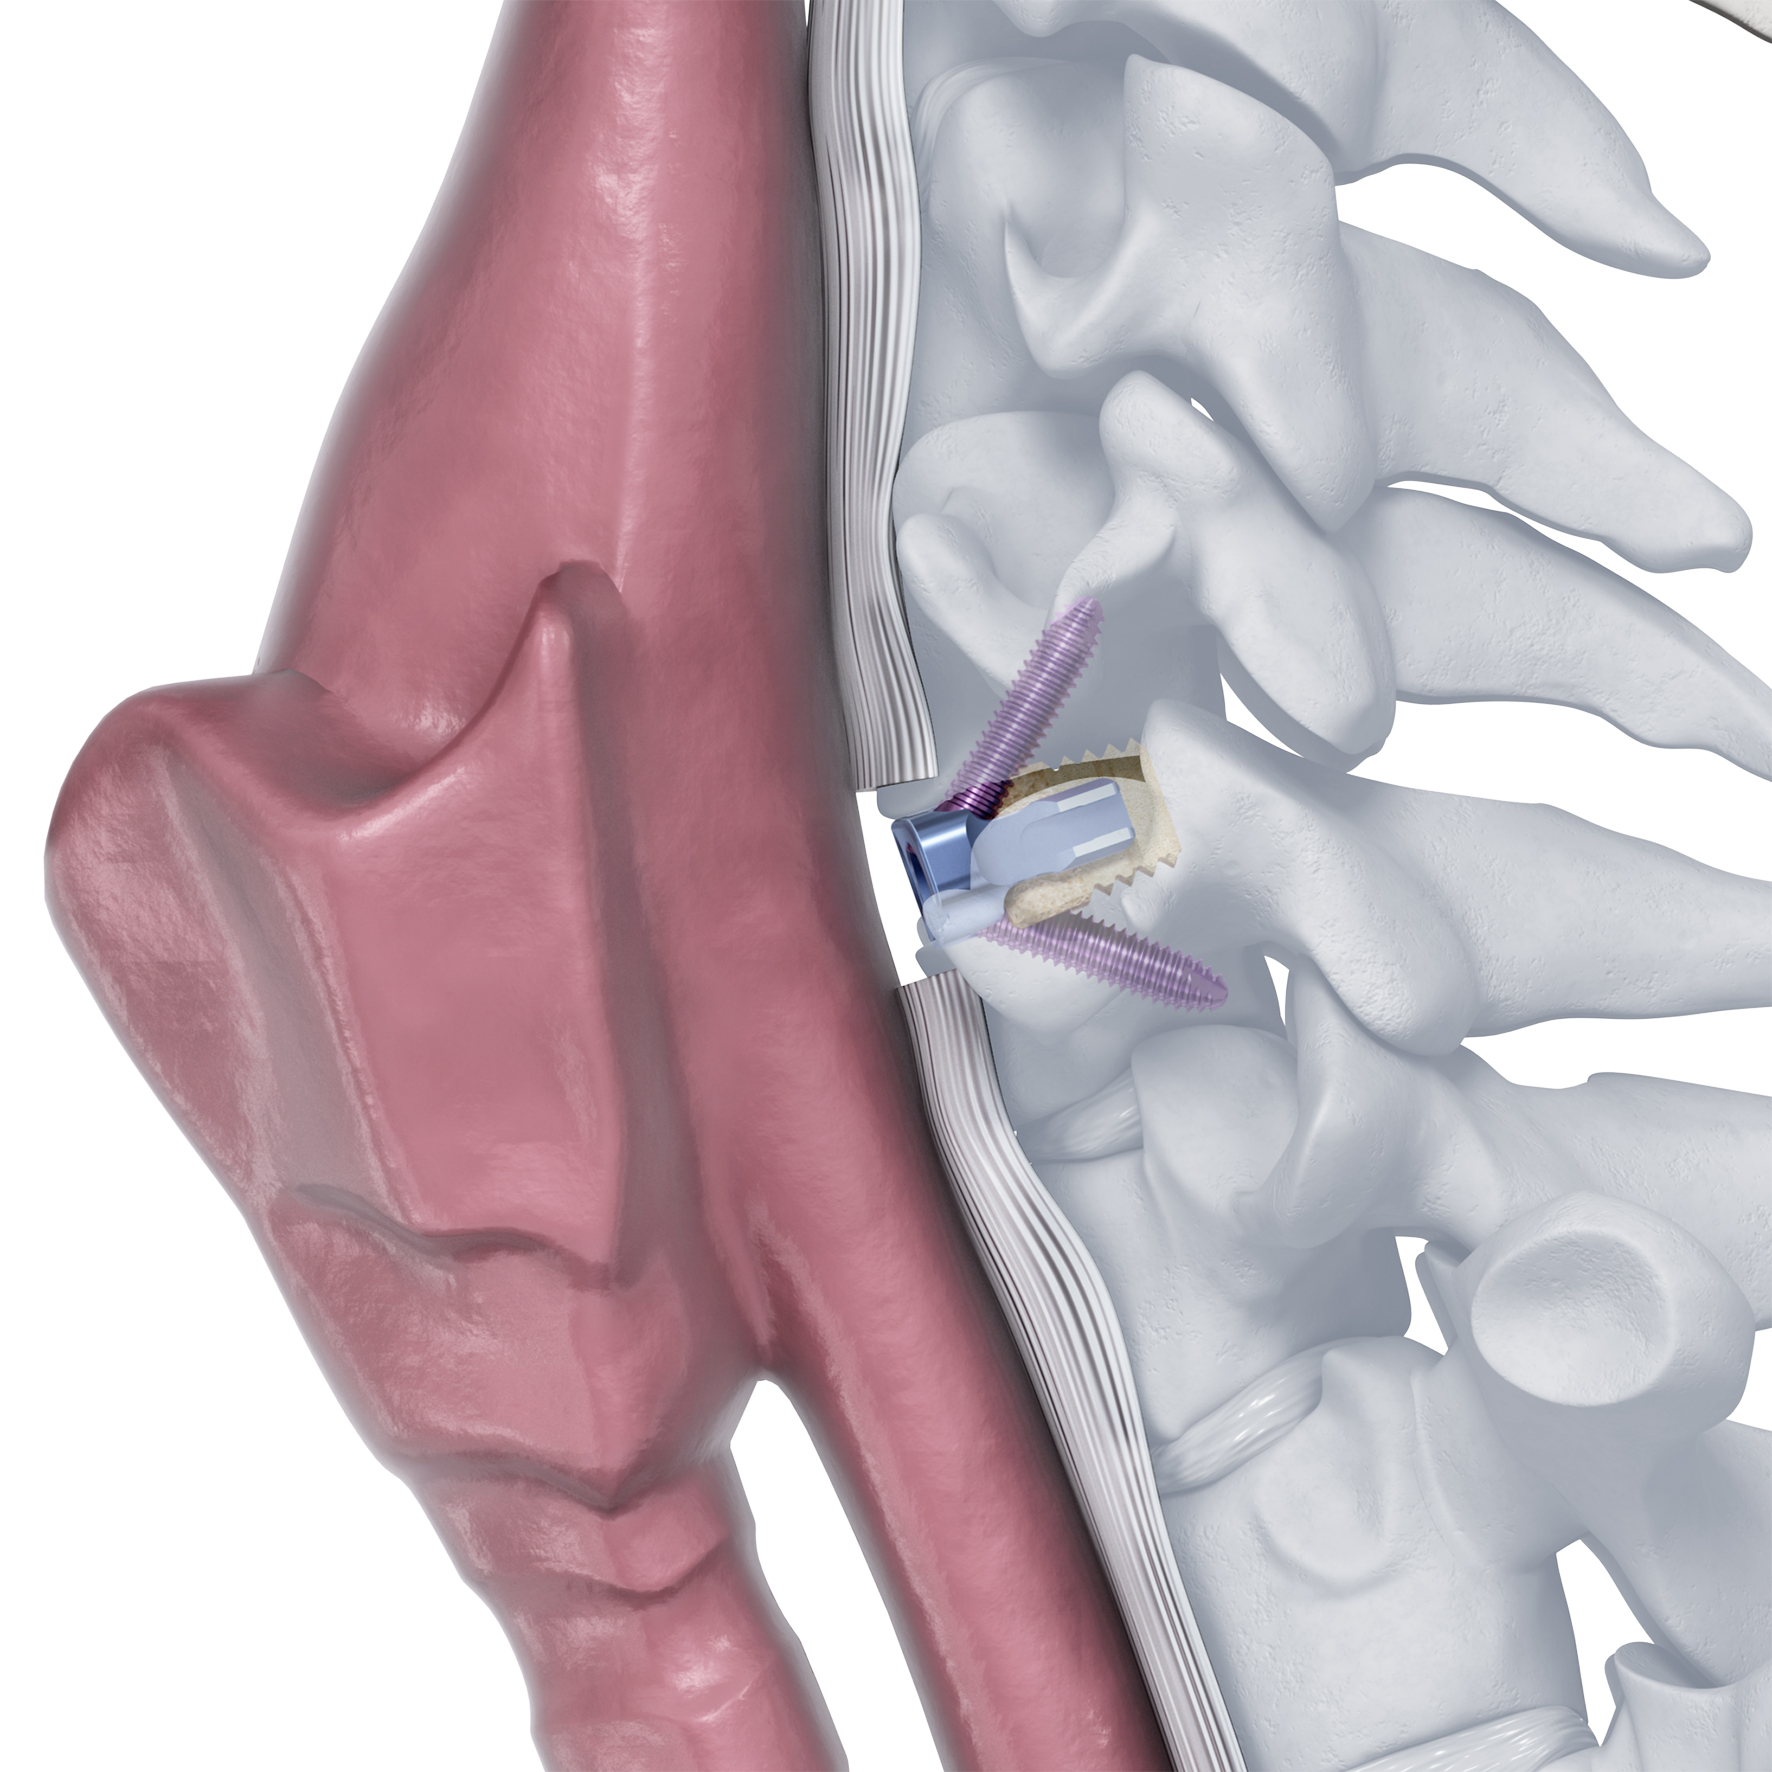

The Zero-P Natural plate is a zero profile anterior cervical plate that provides anterior plate and screw fixation of the cervical spine. The plate is anchored by four locking bone screws, which forms a rigid bone wedge for stability. The plate delivers strength and stability comparable to a traditional cervical plate as demonstrated in mechanical and biomechanical testing [1].

The Zero-P Natural plate was designed for use with the Corticocancellous (CC) Natural allograft spacer processed by the Musculoskeletal Transplant Foundation (MTF) (Fig 1). It features retention arms that are designed to securely attach to the allograft spacer and its height is slightly undersized to the corresponding CC Natural allograft spacer offering potential to avoid stress shielding.

Zero-Profile design to minimize contact with local anatomical structures.

The plate is contained within the excised disc space and does not protrude past the anterior wall of the vertebral body, limiting the risk of damage to vessels and adjacent soft tissue. In addition, preparation of the anterior surface of the vertebral body is not necessary because the plate does not

lie against this surface (Fig 2). It is also designed to prevent contact with adjacent levels. Cervical plates placed near adjacent level discs may contribute to bone formation near or around the adjacent level [2].